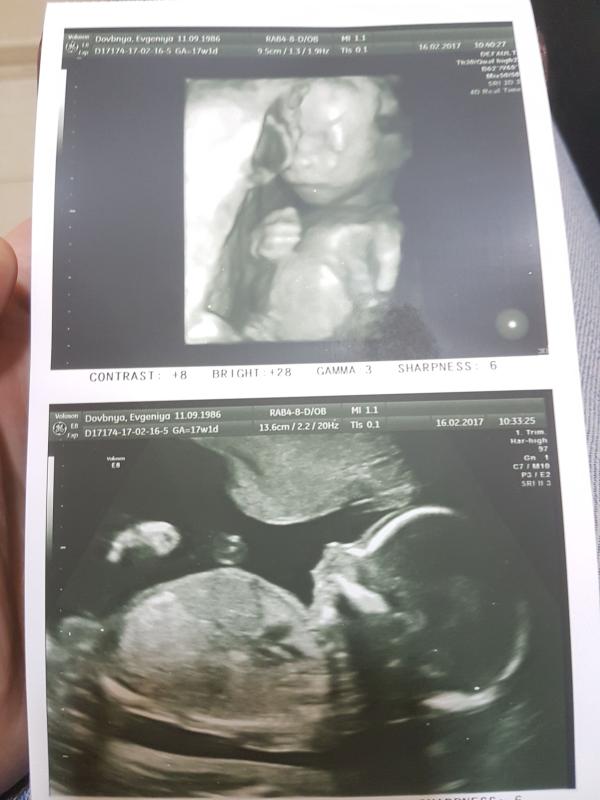

И немного о нас)) с 16 недель мы уже легонько толкаем маму в животик, как я уже говорила будет мальчик, Хотим назвать Львом (хоть родителям и не нравится). И наше фото с Генома.